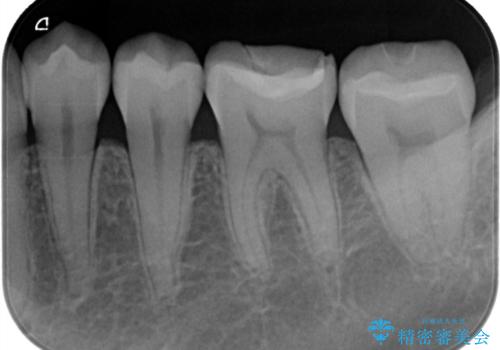

- 銀歯が気になるということで来院された患者様です。

セラミックでの治療を希望されたので治療をいたしました。

銀歯は長い間使用していると隙間ができて、虫歯の原因になります。

そのため適合の良いセラミックをお勧めいたします。